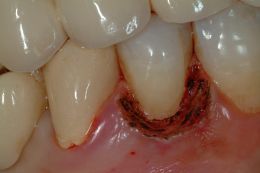

Lesione di classe V coronoradicolare trattate con laser e materiali compositi: una buona rifinitura e lucidatura dei margini dei restauri favorisce la salute parodontale.

Attraverso il laser è stato rimosso il tessuto parodontale che ricopriva buona parte del coletto e del versante coronale permettendoci di lavorare in completa assenza di sangue.